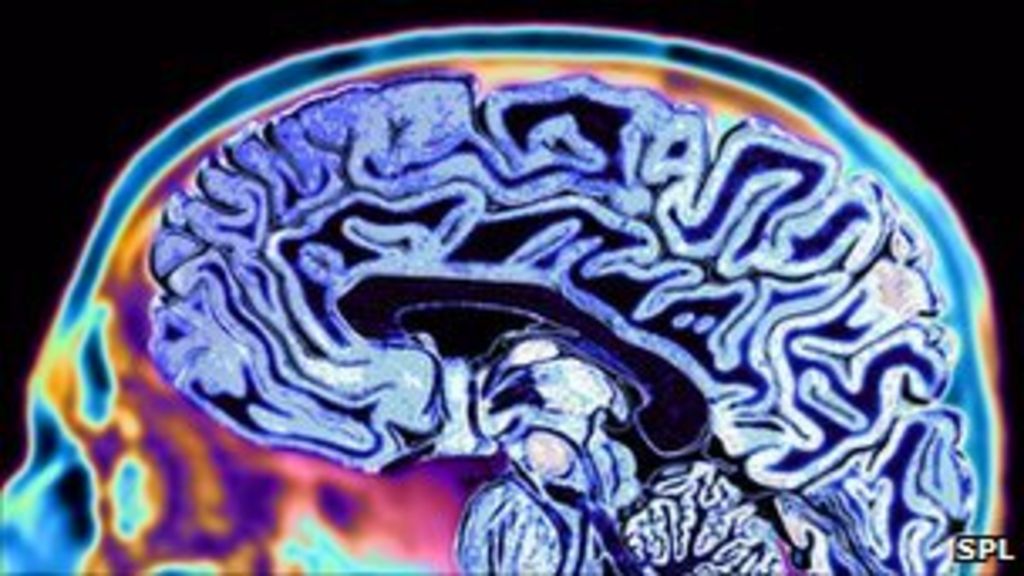

Dream recording device 'possible' researcher claims BBC News Is There A Dream Recorder a team of scientists from atr computational neuroscience laboratories in kyoto, japan used a modified magnetic. in 2013, japanese researchers published a study describing a method for recording dreams by using functional magnetic resonance imaging (fmri) to record brain activity associated with. however, recording dreams would not be without dangers, experts say cnn — although most of. Is There A Dream Recorder.